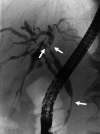

IgG4-related sclerosing cholangitis (IgG4-SC) is a distinct type of cholangitis frequently associated with autoimmune pancreatitis and currently recognized as a biliary manifestation of IgG4-related disease. Although clinical diagnostic criteria of IgG4-SC were established in 2012, differential diagnosis from primary sclerosing cholangitis and cholangiocarcinoma is sometimes difficult. Furthermore, no practical guidelines for IgG4-SC are available. Because the evidence level of most articles retrieved through searching the PubMed, Cochrane Library, and Igaku Chuo Zasshi databases was below C based on the systematic review evaluation system of clinical practice guidelines MINDS 2014, we developed consensus guidelines using the modified Delphi approach. Three committees (a guideline creating committee, an expert panelist committee for rating statements according to the modified Delphi method, and an evaluating committee) were organized. Eighteen clinical questions (CQs) with clinical statements were developed regarding diagnosis (14 CQs) and treatment (4 CQs). Recommendation levels for clinical statements were set using the modified Delphi approach. The guidelines explain methods for accurate diagnosis, and safe and appropriate treatment of IgG4-SC.